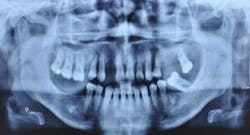

Fig. 2: Anterior teeth relationships prior to treatment

Diagnosis

The patient’s main problem is adult aggressive periodontitis, aggravated by tobacco use. The consequent tooth losses have caused migrations of the remaining teeth under functional adaptation.